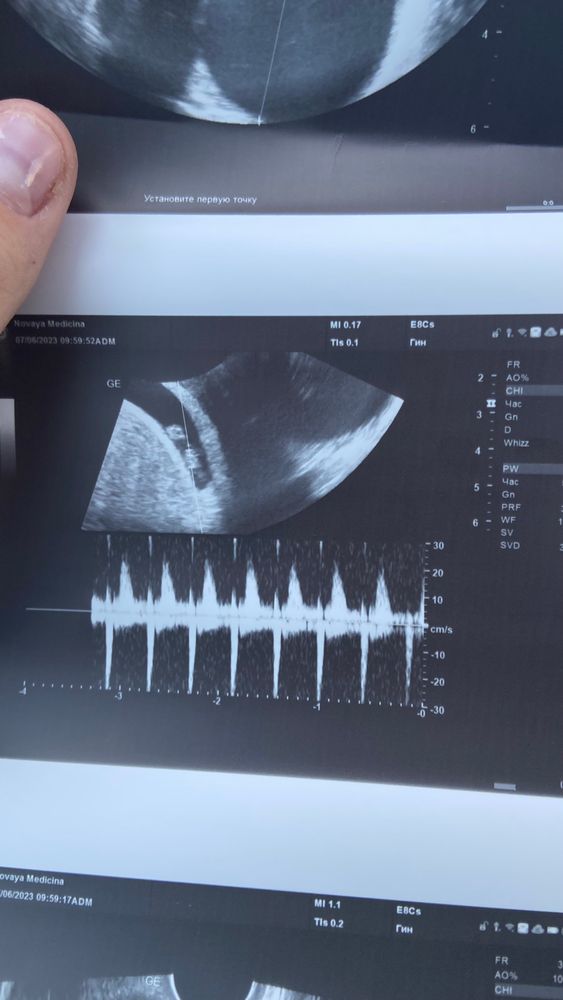

Карина Москвичева, очень рада за вас! А пя сколько? сердечко слышали? Мне вот не дали, может и не должны были, интересно😄

Лилия, пя 34 мм, частота сердцебиение 145, жм 4,4 мм, сердечко сразу включили

Карина Москвичева, теперь мне обидно, что не дали сердце послушать сказали просто, есть сердцебиение )) и все

Лилия, и вам дадут послушать я сама не ожидала что его включат )) но рада что услышала и теперь спокойна как удав

Карина Москвичева, но Рада, что у нас с вами все ок Изображение